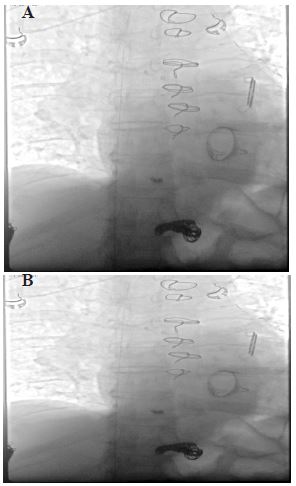

An attempt was made to retrieve the coil via fluoroscopy by interventional radiologist but was unsuccessful. The coil was adherent to the anterior right ventricular wall, and it was felt to be at a low risk of further embolization. Due to the patient’s advanced age and comorbidities, no further attempts were made at retrieving the coil, given the risk-benefit ratio. There was no family or personal history of Hereditary Hemorrhagic Telangiectasia (HHT) nor any symptoms or clinical signs suggestive of HHT. However, given the spontaneous development of portosystemic shunt and hematuria, he was referred to the genetics outpatient clinic for further testing.

Figure 2: Fluoroscopy in the anteroposterior and lateral view showed an attempt at retrieving the small embolised coil at the anterior wall of the heart with a snare.